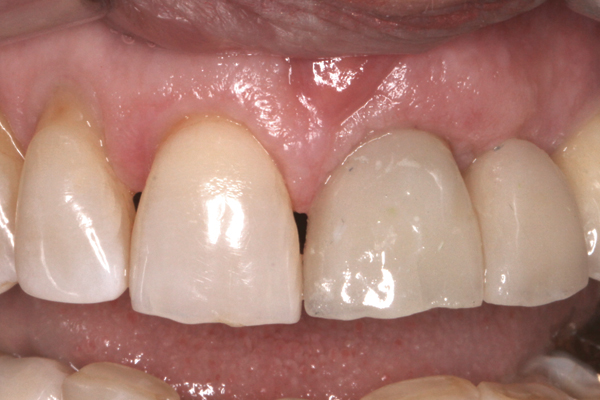

Fig 17. Creation of the final soft-tissue architecture during the provisional stage provides a superior level of predictability and will minimize the chance of tissue changes following placement of the definitive restoration.

Figure 17